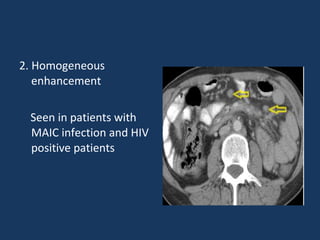

2. Homogeneous

enhancement

Seen in patients with

MAIC infection and HIV

positive patients

2. Homogeneous enhancement Seen inpatients with MAIC infection and HIV positive patients